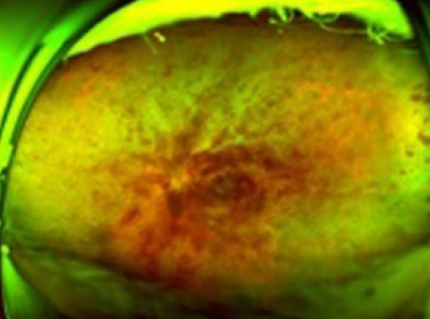

網膜中心静脈閉塞

網膜静脈の根幹部が詰まって全体に出血が広がります。

静脈の流れが悪くなることにより、むくみ(黄斑浮腫)や出血がおこることで急に視力が低下したり、視野の一部が欠けて見えたり、ゆがんで見えたりします。